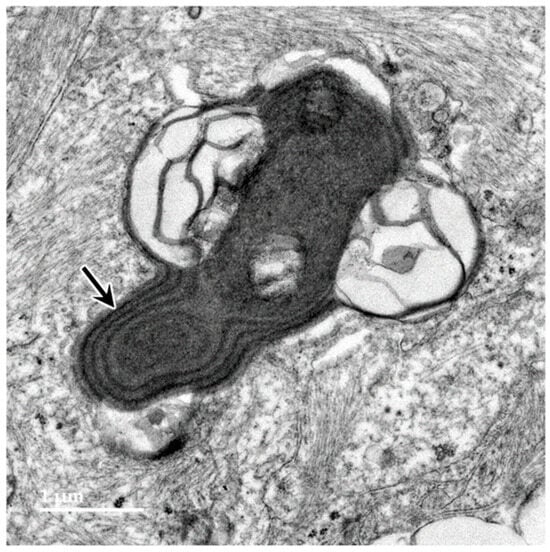

3.1. Microscopic Findings